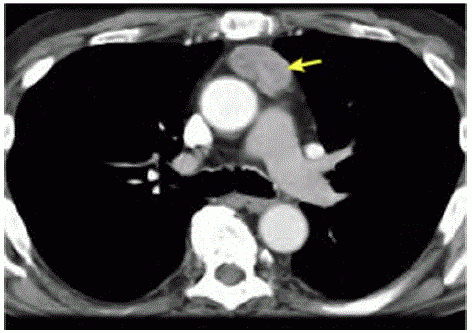

Ulna paciente de 47 anos de idade, com sint01nas gripais agudos, realizou exames de imagem de tórax por suspeita de Covid-19. A hipótese não se confirmou, porém a tomografia computadorizada de tórax, representada pela imagem a seguir, evidenciou uma massa heterogênea de contornos bem definidos em topografia de mediastino anterior, em localização de timo, de aproximadamente 4,5 cm x 2,9 cm. Não apresentava linfonodos aumentados no exame de imagem. Realizaram-se , ainda, tomografias computadorizadas de encéfalo e de abdome, que não mostraram alterações.

Acervo Pessoal